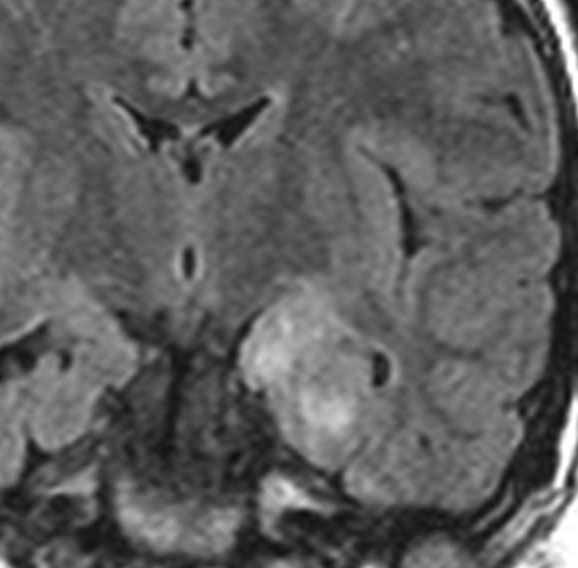

小児の良性の神経節膠腫 ganglioglioma グレード1(真の腫瘍)

7才の時に音読でつかえるようになり,眼で何かを追っているような欠伸発作(左側頭葉てんかん)を繰り返すようになり,強直間代発作を生じて腫瘍が発見されました。下側頭回底面の皮質に発生した境界明瞭な腫瘍であり,周囲に脳浮腫を伴っています。T2強調画像で線維成分の多い硬い部分は低信号に,軟らかい部分はやや高信号となり,ガドリニウムでheterogenousに増強されます。グレード1の神経節膠腫としては非典型的な画像所見で術前診断は難しいもので,PXA pleomorphic xanthoastrocytoma も疑いました。もちろん治療としては開頭手術での全摘出です。術後に発作は消失しています。

構成要素はGFAP陽性の膠細胞が多く認められます。神経細胞様形態の細胞 ganglion cellではNeuN(+), CGA (+) synaptophisin (++), neurofilament (+)です。大型で腫大した核を有して核内封入体構造を有する好酸性もしくは淡明な細胞質を有する細胞が増殖してPXAを考えさせる部分像もありました。granular bodyも認められて,右の写真のように膠原線維の増生が目立つ部分もあります。これは表面の非常に硬い線維性の腫瘍部分です。MIB-1 indexは4%とやや高い値です。BRAF v600Eの変異が認められました。